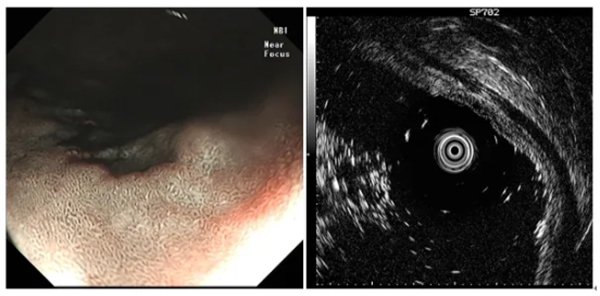

圖示髮(fa)現(xian)消化道早癌并利用(yong)超聲內(nei)鏡判斷(duan)其浸潤深度